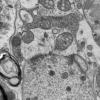

Neuroaxonal dystrophy (3)